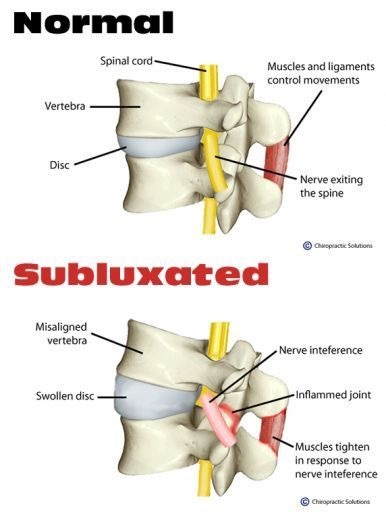

Subluxation (サブラクセーション)

Subluxation (サブラクセーション)

脊柱解剖学(Spinal Anatomy)

脊柱解剖学(Spinal Anatomy)